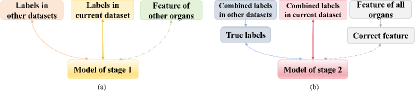

Our method consists of two stages, with each stage leveraging complementary information across datasets to enhance model performance. In the first stage, each student model is trained under supervision not only from the labels of the current dataset but also from the labels of other datasets and the features extracted by other models, as shown in Fig. 2 (a). This stage enhances each model’s ability to segment the current organ and improves the quality of pseudo labels, resulting in high-quality, fully labeled datasets with pseudo labels. In the second stage, each student model is supervised by the combined labels of the current dataset and the true labels from other datasets, while also being supervised by the correct features dynamically conveyed by other models in the latent space, as shown in Fig. 2 (b), thus making full use of supervision information to improve the performance of multi-organ segmentation. The framework we proposed is capable of accommodating varying numbers of labeled organs across different datasets, including those contain multiple labeled organs.